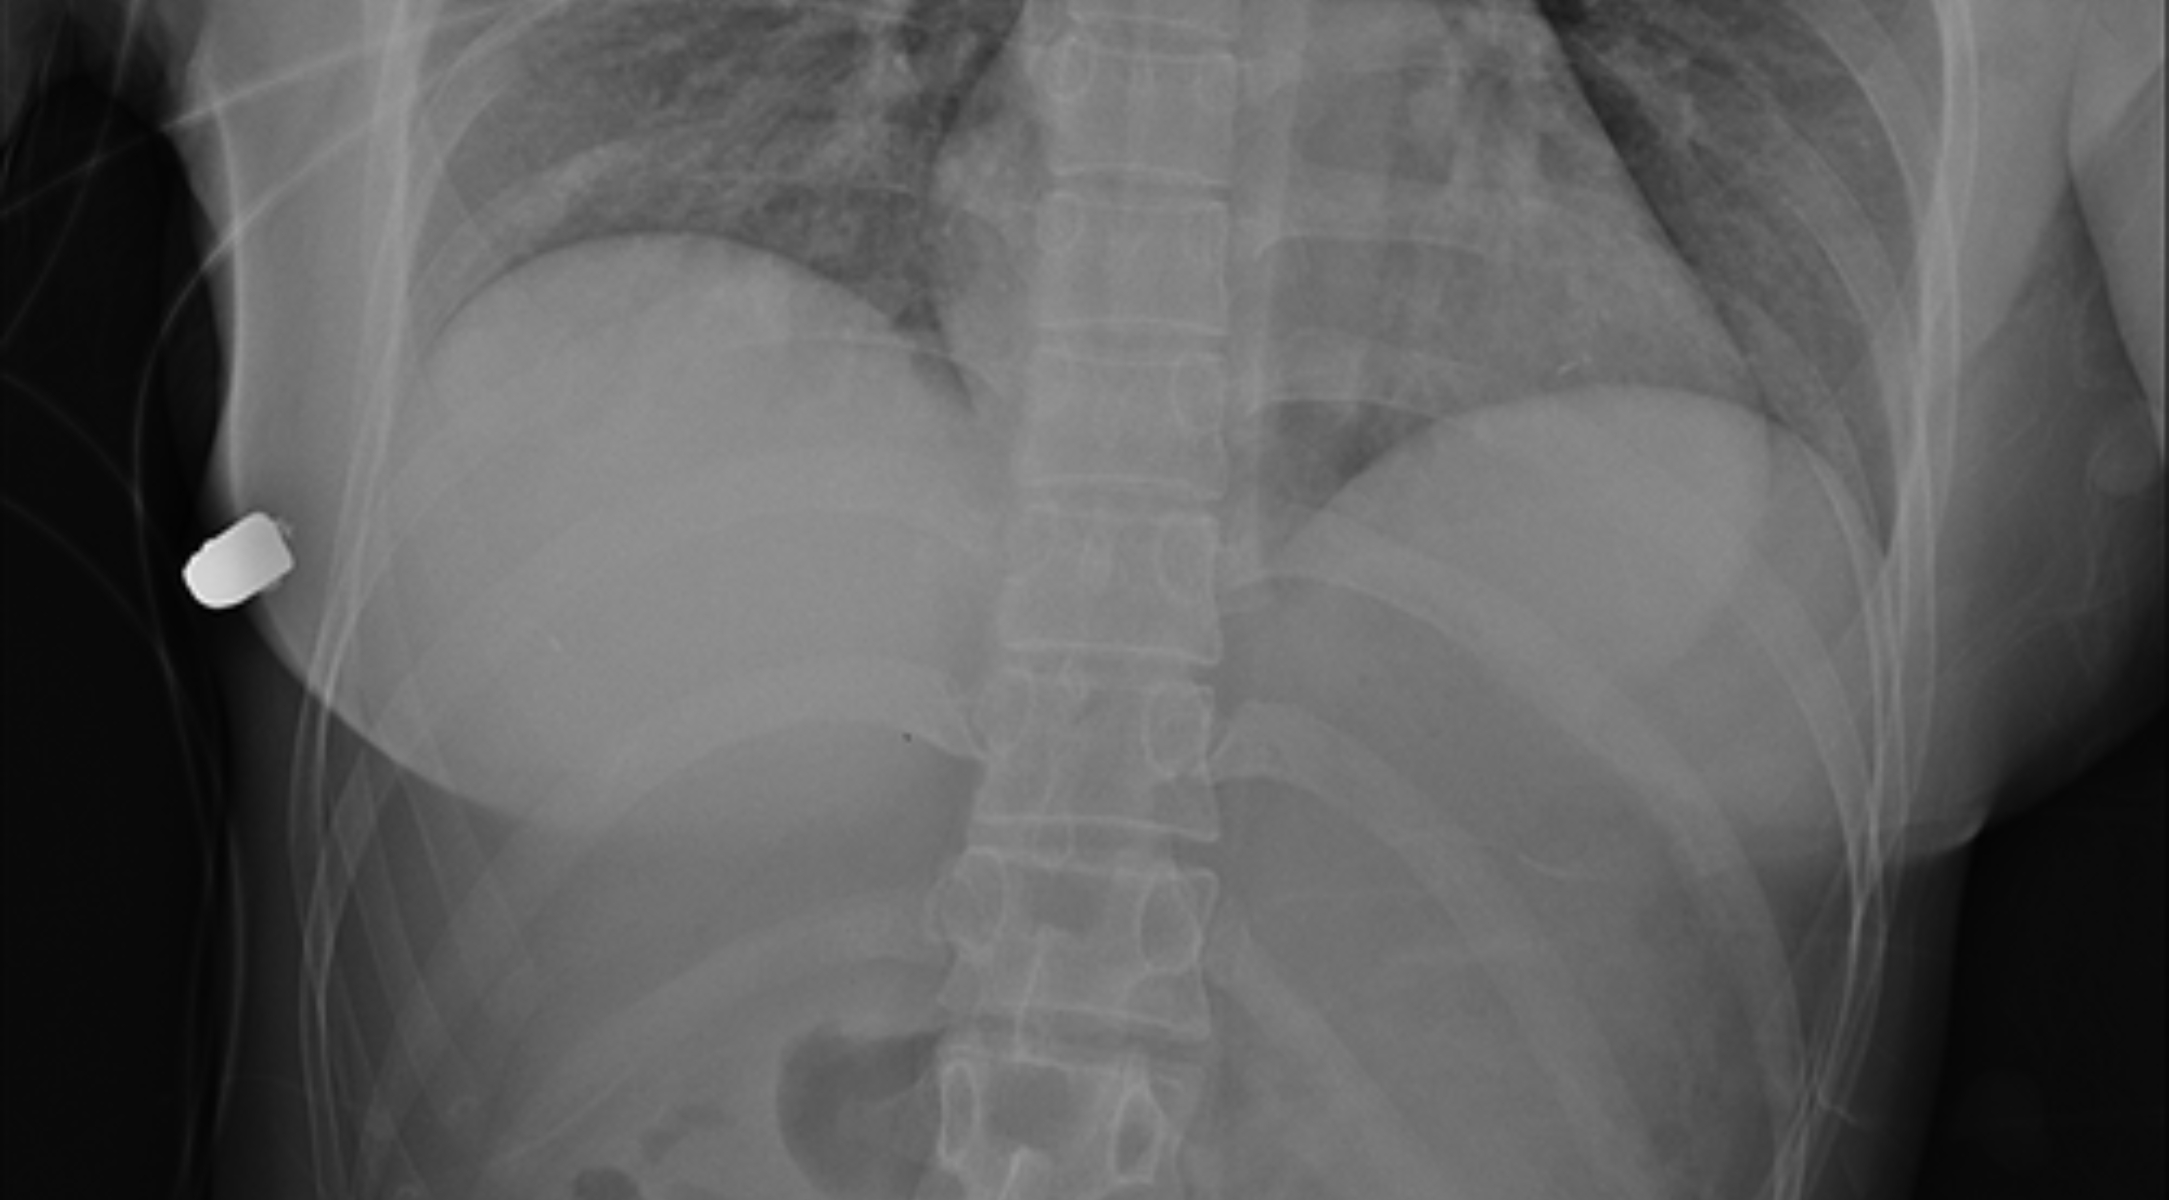

Mujer se salva de morir de un disparo gracias a sus implantes de senos

Una mujer de 30 años fue impactada por una bala mientras caminaba por una calle de Ontario, Canada, pero afortunadamente se salvó de morir gracias a sus implantes mamarios.

La mujer empezó a sentir dolor en un seno izquierdo y notó que estaba sangrando, razón por la que fue trasladada de manera inmediata a la Clínica McLean, en donde los trabajadores de salud encontraron una bala.

Los médicos aseguraron que el implante logró salvar la vida de la mujer, pues la bala iba en dirección a su corazón. Giancarlo McEvenue, cirujano plástico que retiró la bala del cuerpo de la mujer, afirmó:

“Este implante cubre el corazón y la cavidad intratorácica, así que probablemente le salvó la vida a la mujer”.

Una fractura en una costilla y daño en el tejido pulmonar, fueron las dos consecuencias que sufrió la mujer por el impacto de la bala, que podría haberla matado.